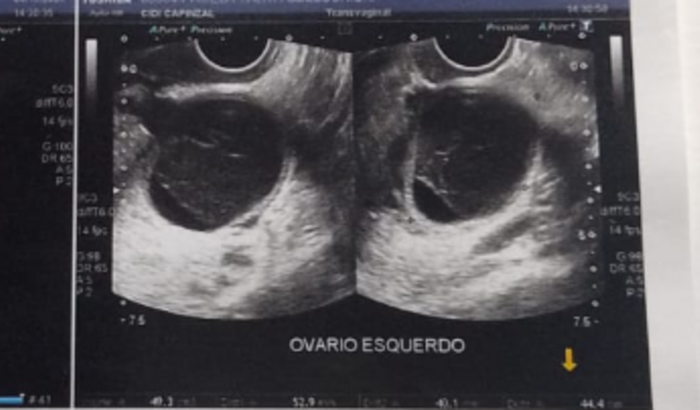

Descobri que estou com um cisto septado com características malignas e ele está quase do tamanho do meu útero, está extremamente grande e crescendo a cada dia.

O médico orientou a retirar com emergência, não ficar esperando pois pode ter muitas complicações, além da grande chance de ser um câncer maligno, pois tem um histórico imenso de cancer nos dois lados da minha família; Porém, para termos certeza é somente fazendo essa cirurgia para fazer a biópsia.